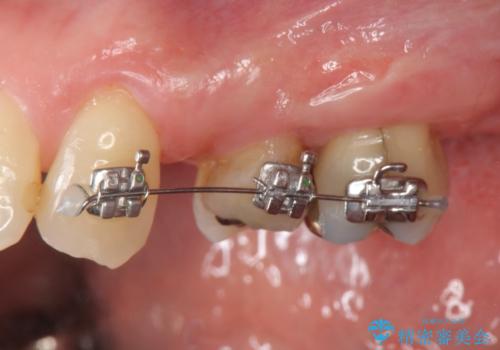

ブリッジの長期的な予後のためには支台となる歯の位置・清掃性が重要となりますが、今回ブリッジを製作するにあたり位置の悪い左上小臼歯を補綴前小矯正を行い位置を改善します。

補綴前小矯正について

矯正を行うことで歯を適切な位置に動かすことでより、清掃性に優れ長期的な予後を見込むことのできるブリッジを製作することができました。